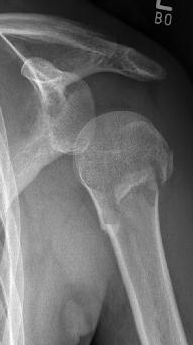

Proximaler Oberarmbruch5Proximaler Oberarmbruch6

Picture: Here is a subcapital upper arm break in a young woman. An angle stable plate osteosynthesis was performed to stabilize the head in correct position to the humeral shaft and shoulder joint. Especially in young patients, We strive to treat non-invasively and as gently as possible. This possibility is often due to the bone quality in young as opposed to older people.